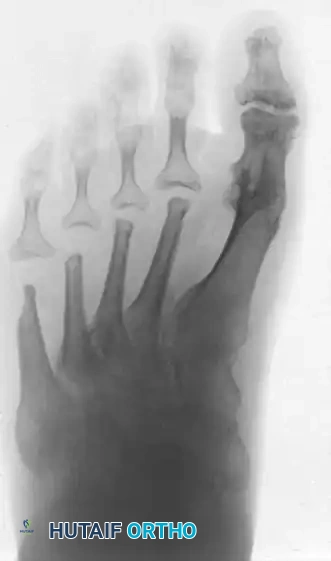

The classic "rheumatoid foot" presents with severe hallux valgus, dorsal subluxation or frank dislocation of the lesser metatarsophalangeal (MTP) joints, claw toes, hammer toes, and the formation of painful adventitial bursae. As the proximal phalanges subluxate dorsally, the plantar metatarsal fat pad is drawn distally, leaving the prominent metatarsal heads directly exposed to plantar pressure, leading to intractable plantar keratoses and ulceration.

Forefoot arthroplasty is directed primarily at the severe metatarsophalangeal joint deformities. The overarching goals are to relieve pain, correct deformity, improve cosmesis, enhance ambulatory function, and allow the patient to wear a reasonable variety of footwear.

Resection of all five metatarsal heads, or fusion of the first MTP joint combined with resection of metatarsals 2 through 5, have both been shown to produce excellent results. All four of the lesser toes must be treated in the same manner, regardless of the varying severity of involvement of each individual ray. While there are rare exceptions where only one or two lesser metatarsal heads are removed, the patient must be warned that subsequent surgeries to remove the remaining heads are highly likely as the disease progresses.

ARTHRODESIS OF THE FIRST METATARSOPHALANGEAL JOINT

For the rheumatoid hallux, arthrodesis of the first MTP joint, combined with varying degrees of bony shortening/resection at the lesser MTP joints, is the gold standard. This approach yields satisfactory results in 80% to 90% of patients.